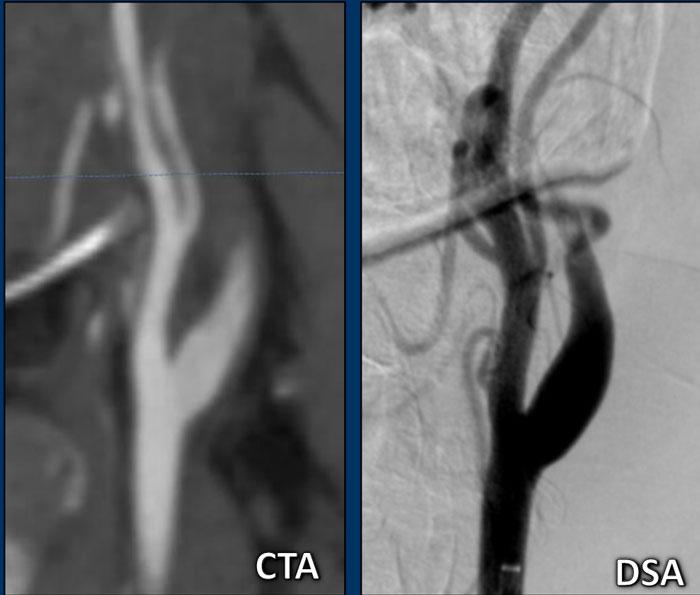

ICA hình ngọn lửa (Flame-shaped ICA)

Các hình ảnh này cho thấy hình ảnh điển hình dạng ngọn lửa của bóc tách động mạch cảnh trên tái tạo CTA mặt phẳng đứng dọc (sagittal) và DSA.

Lưu ý rằng trên tái tạo CTA, bạn có thể theo dõi đường viền của ICA bị giãn phía trên mức mà thuốc cản quang dừng lại.

Cũng cần lưu ý sự tương đồng đáng kể giữa hình ảnh CTA và DSA khi so sánh hai phương thức này.

Dấu hiệu sợi chỉ (String sign)

Trong hầu hết các trường hợp, bóc tách mạch máu sẽ biểu hiện với hình ảnh dạng ngọn lửa như trong hình A, nhưng khi lòng mạch bị chèn ép ít hơn và vẫn còn thông một phần, bạn có thể thấy “dấu hiệu sợi chỉ” như trong hình B.